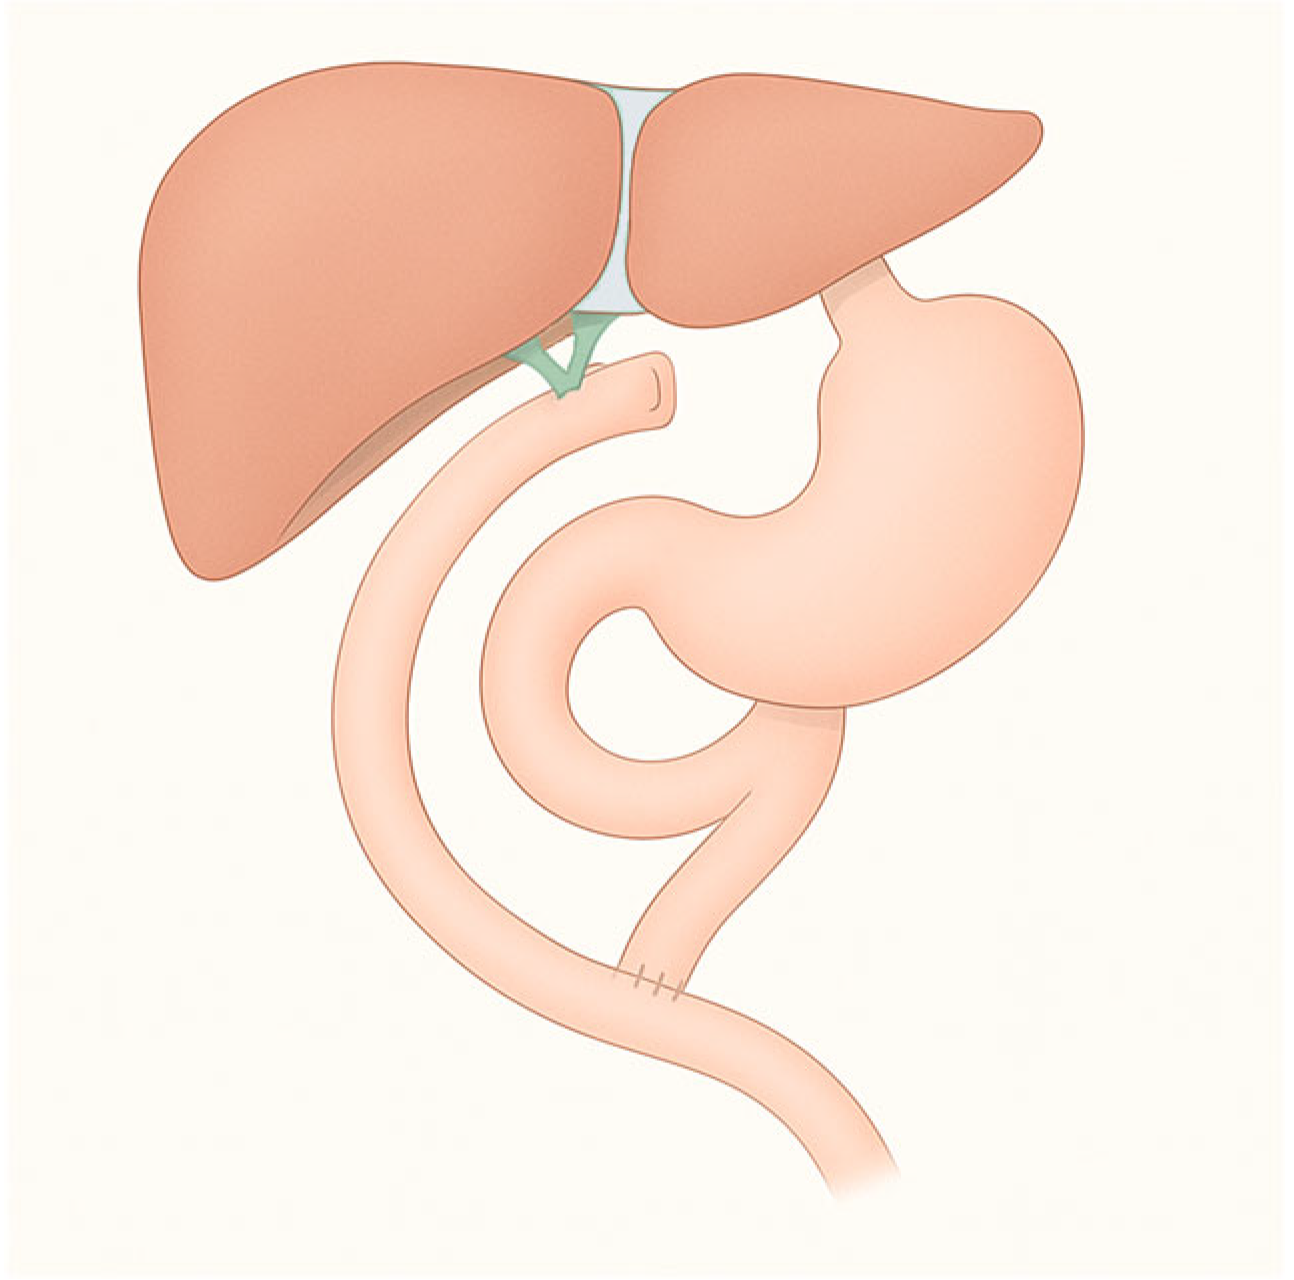

Figure 3. Gastric bypass.

3.3. Roux-en-Y Gastric Bypass (RYGB)

RYGB is the most widely performed bariatric procedure worldwide. It consists of creating a small gastric pouch anastomosed to the jejunum, bypassing the excluded stomach and duodenum (Figure 3). This operation was originally designed for weight loss but is now equally valued for its metabolic benefits in patients with type 2 diabetes and severe obesity. Variations in limb length are frequent: long biliopancreatic or alimentary limbs are often employed in super-obese patients or those with severe metabolic disease to increase malabsorptive effects. An alternative is the mini-gastric bypass, in which a long gastric pouch is anastomosed directly to a jejunal loop. Despite its effectiveness in reducing calorie intake and weight loss, it carries the risk of bile reflux, which remains a subject of ongoing debate and study [8].